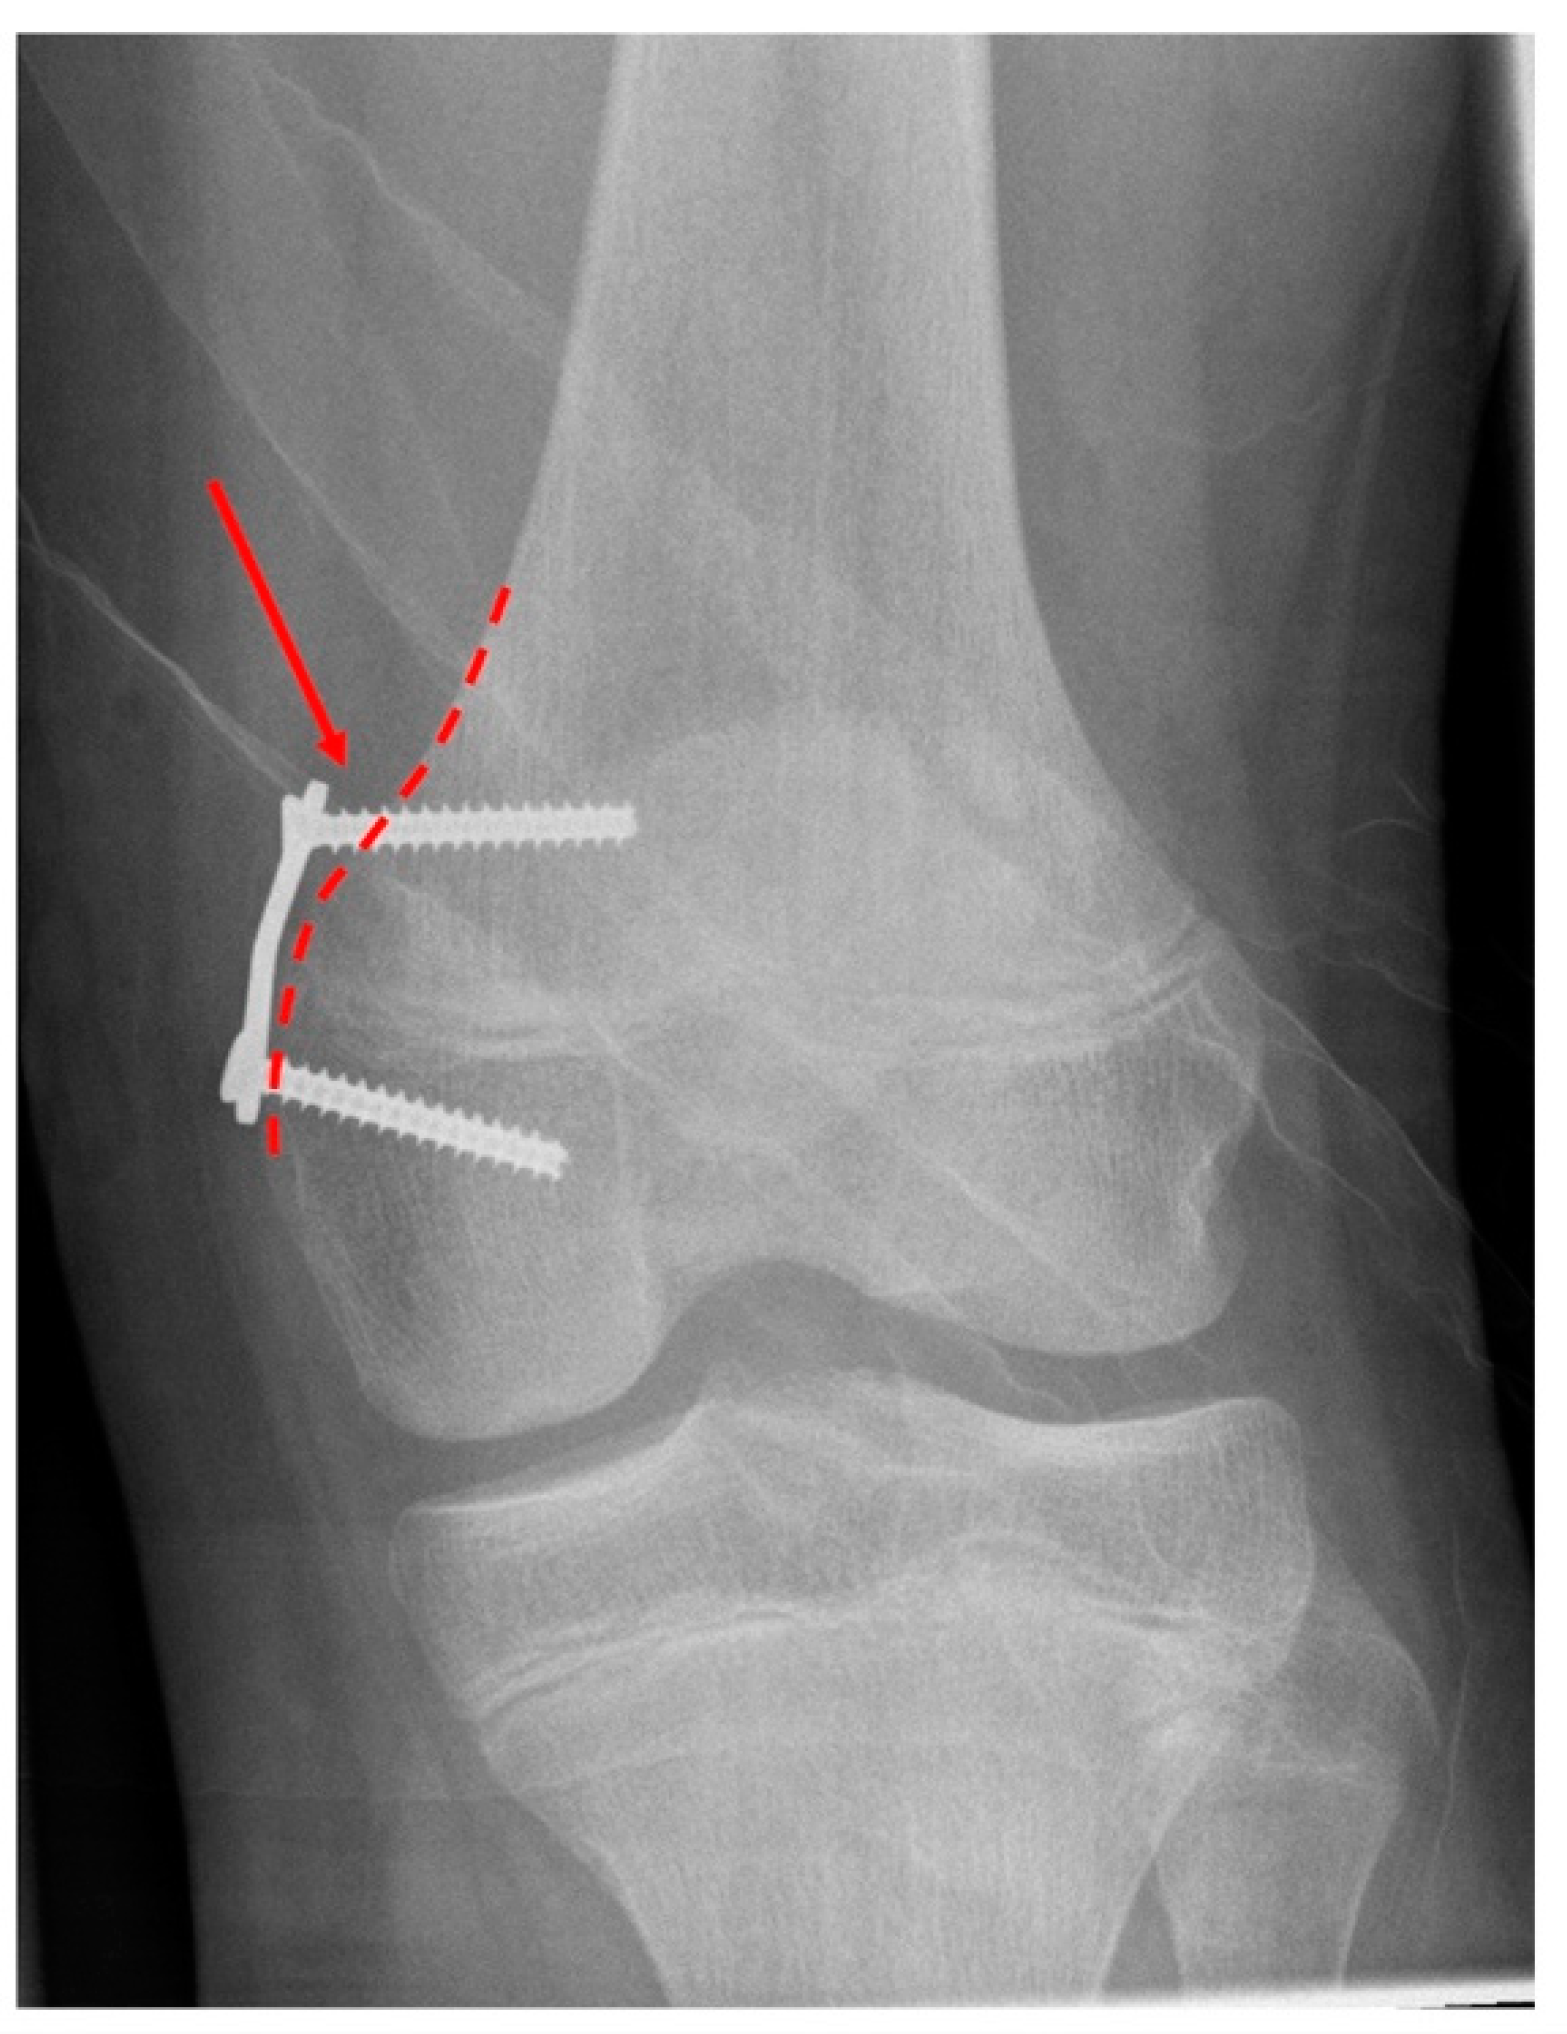

Figure 3 from Metaphyseal Screw Migration After Medial Patellofemoral Metaphyseal Screw Synthes Original instruments and implants of the association for the study of internal fixation — ao asif synthes screw reference chart reference chart screws, drill bits, taps locking screws, guide. The 2.7 mm/3.5 mm va lcp™ ankle trauma system is a comprehensive plating system that merges variable angle locking screw technology with conventional. Lcp metaphyseal plate for distal medial tibia. Use. Metaphyseal Screw Synthes.

An example how a removal of only a metaphyseal screw can be performed Metaphyseal Screw Synthes Use the lcp metaphyseal plate according to the lcp principles (see lcp instructions for use, art. Lcp metaphyseal plate for distal medial tibia. Original instruments and implants of the association for the study of internal fixation — ao asif synthes screw reference chart reference chart screws, drill bits, taps locking screws, guide. 6 synthes lcp locking compression plate ordering information. Metaphyseal Screw Synthes.